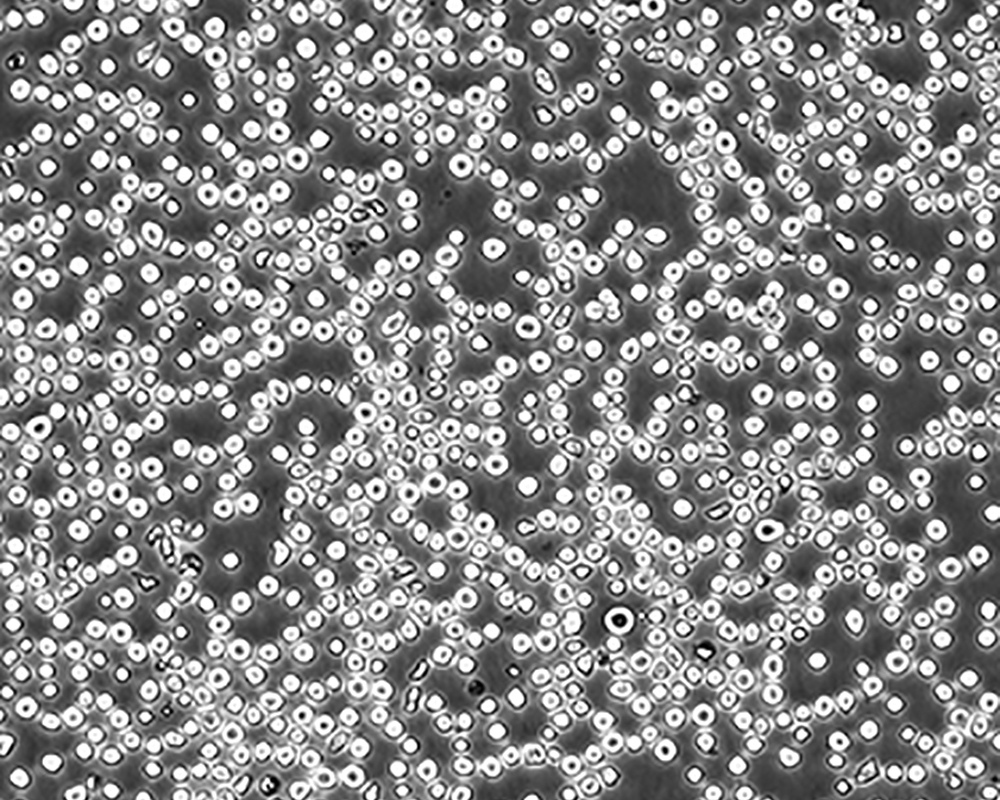

生長特性 suspension

形態特征 lymphoblast

細胞描述 CEM/C1是人T細胞白血病細胞株CCRF-CEM(見ATCC CCL-119)具有喜樹堿抗性的衍生株。1991年細胞株選擇并亞克隆了對CPT的抗性。細胞表現出對CPT類似物水溶性的托泊替康和非水溶性的9-氨基-CPT及10,11-亞甲二氧基-CPT具有交叉抗性。CEM/C1細胞對CPT的敏感性較母系CEM細胞低31倍。CEM/C1細胞表現非典型的多藥抗性和轉換拓補異構酶I催化活性。對CPT的抗性維持6個月以上。